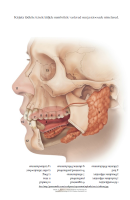

Teises peatükis tutvutakse suuõõne sisemusega, erinevate hambatüüpide ja nende funktsioonidega.

Samuti õpitakse tundma hamba ehitust ning selgitatakse piima- ja jäävhammaste ning sülje tähtsust.